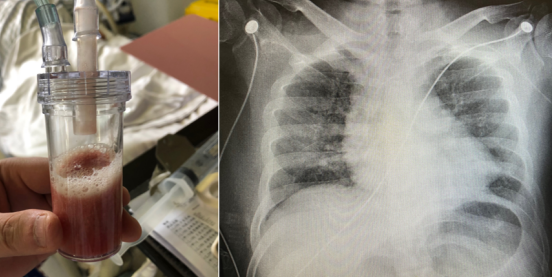

患者主诉“发作性胸痛8个月,加重2周,胸闷气促1周”。8个月前无明显诱因感心前区疼痛,针刺样,持续时间短。无放射痛,口服麝香保心丸可缓解。2022年6月至我院心内科就诊,冠脉造影提示冠脉狭窄,拒绝支架植入,近2周胸痛加重,双下肢水肿加重,1周前出现胸闷气急进行性加重,不能平稳,咳嗽咳血性分泌物,外院给予无创通气治疗,1天前急诊收治我院心内科监护室。入院诊断“冠心病,高血压病3级,2型糖尿病,脑梗死后遗症”。胸片显示心脏增大,两肺渗出明显。

图片